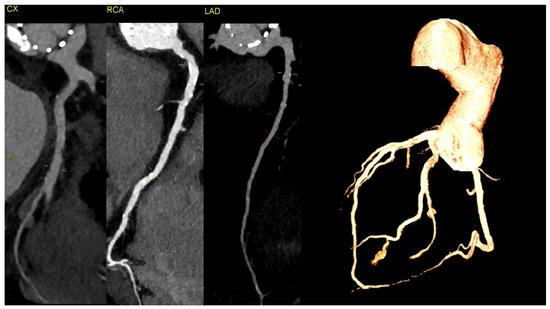

Figure 3. The CT discluded significant coronary artery stenosis (Cx—circumflex artery, RCA—right coronary artery, LAD—left anterior descending artery). The myocardial infarction was treated conservatively with anticoagulation due to the presence of aortic graft and valve thrombosis, and it led to the resolution of the chest pain. The clinically insignificant lesions in the coronary arteries on CT were suggestive of the fact that NSTEMI could be caused by the occlusion of the ostium of the arteries by the aortic valve thrombus.